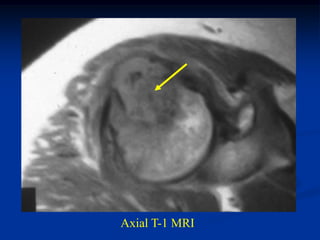

Case #556

55 year male with

enchondroma tibia

Lateral view

Axial T-1 MRI

tumor

Axial T-2 MRI

Biopsy photomic